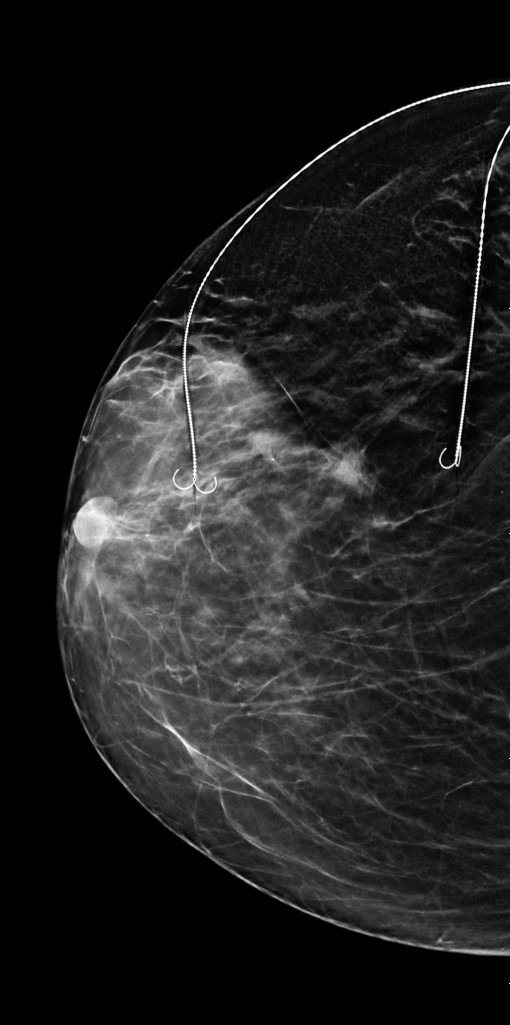

La Spitalul Județean Constanța, în cadrul Secției Chirurgie I, coordonată de Prof. Univ. Dr. Răzvan Popescu, a fost realizată în premieră o intervenție chirurgicală de conservare a sânului în cazul unei paciente cu trei leziuni maligne, prin tehnica Bracketing cu două harpoane.

Intervenția a fost realizată de o echipă medicală multidisciplinară formată din:

• Iulia Dogaru – chirurgie

• Cristina Bustiuc – medic primar ATI

• Alexandru Gavrilă – medic primar radiologie și imagistică medicală, competență în senologie